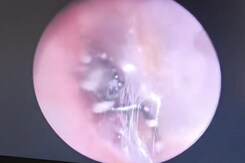

Human Teeth Found In Chinese Sausages, Dim Sum, Spark Concern Over Food Safety

A woman from Jilin province discovered three artificial teeth in a sausage she bought for her child from a street stall